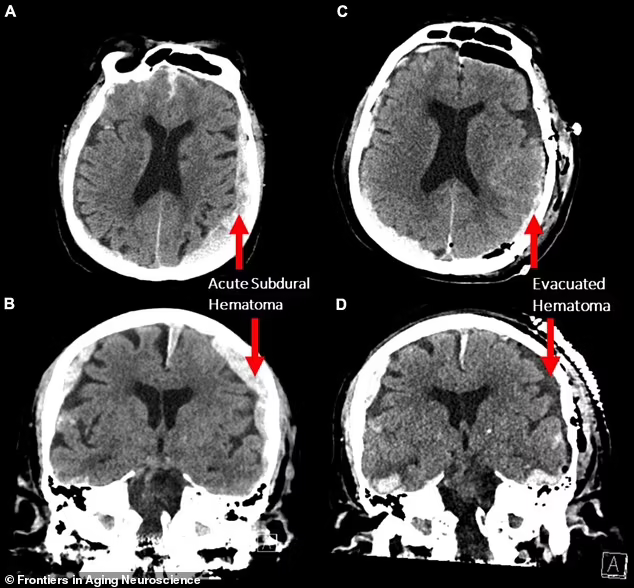

据报道,不列颠哥伦比亚省温哥华综合医院收治了一名癫痫发作的87岁男子,患者心脏骤停。当神经科学家使用脑电图(EEG)为其检测和治疗时,无意中记录到一个濒临死亡的大脑活动。